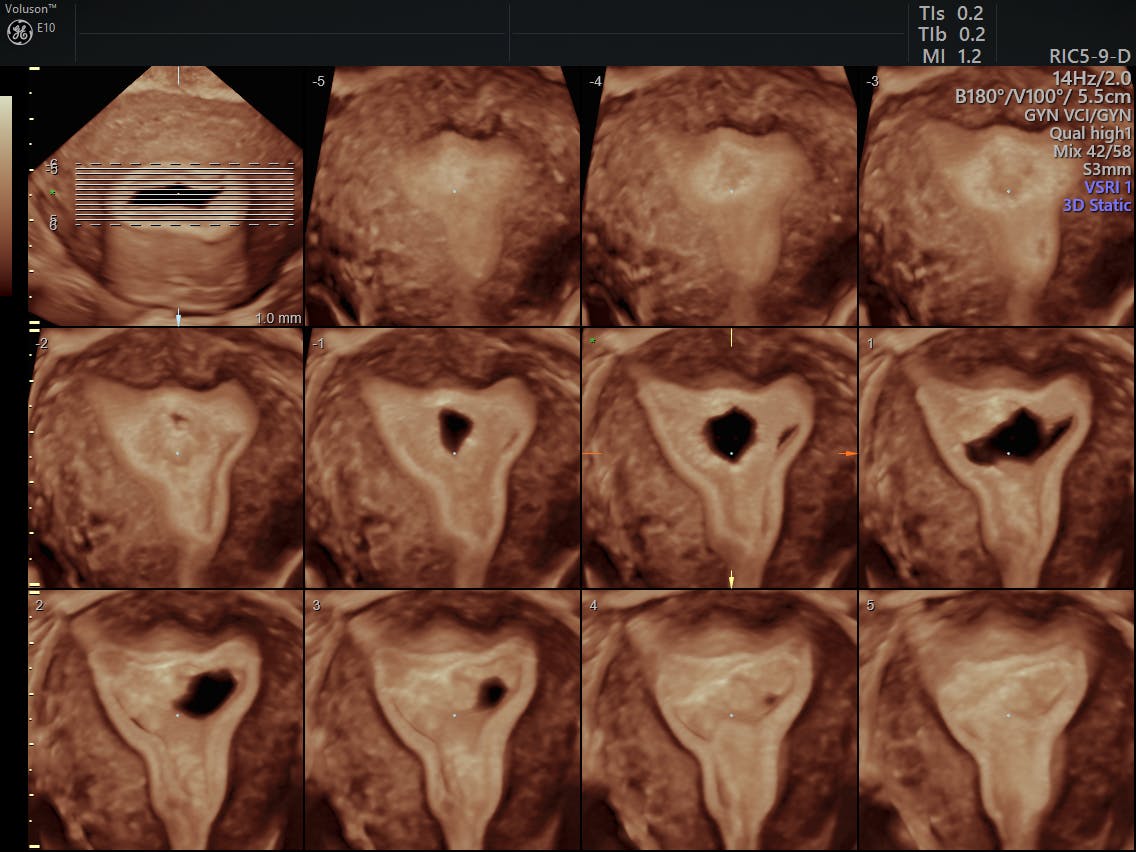

High frequency sound waves are used to create a picture of the uterus. In this plane you should be able to assess the uterus vagina and cervix. The safety of 3d and 4d ultrasounds during pregnancy. Obtaining a 3d coronal image of the uterus.

Volume acquisition for 3d ultrasound requires specialized ultrasound systems and transducers. A transvaginal compared to the transabdominal approach is generally preferred due to the higher frequency of the probe and the proximity to the pelvic organs which improve image resolutionan adequately enlarged mid sagittal or transverse section of.